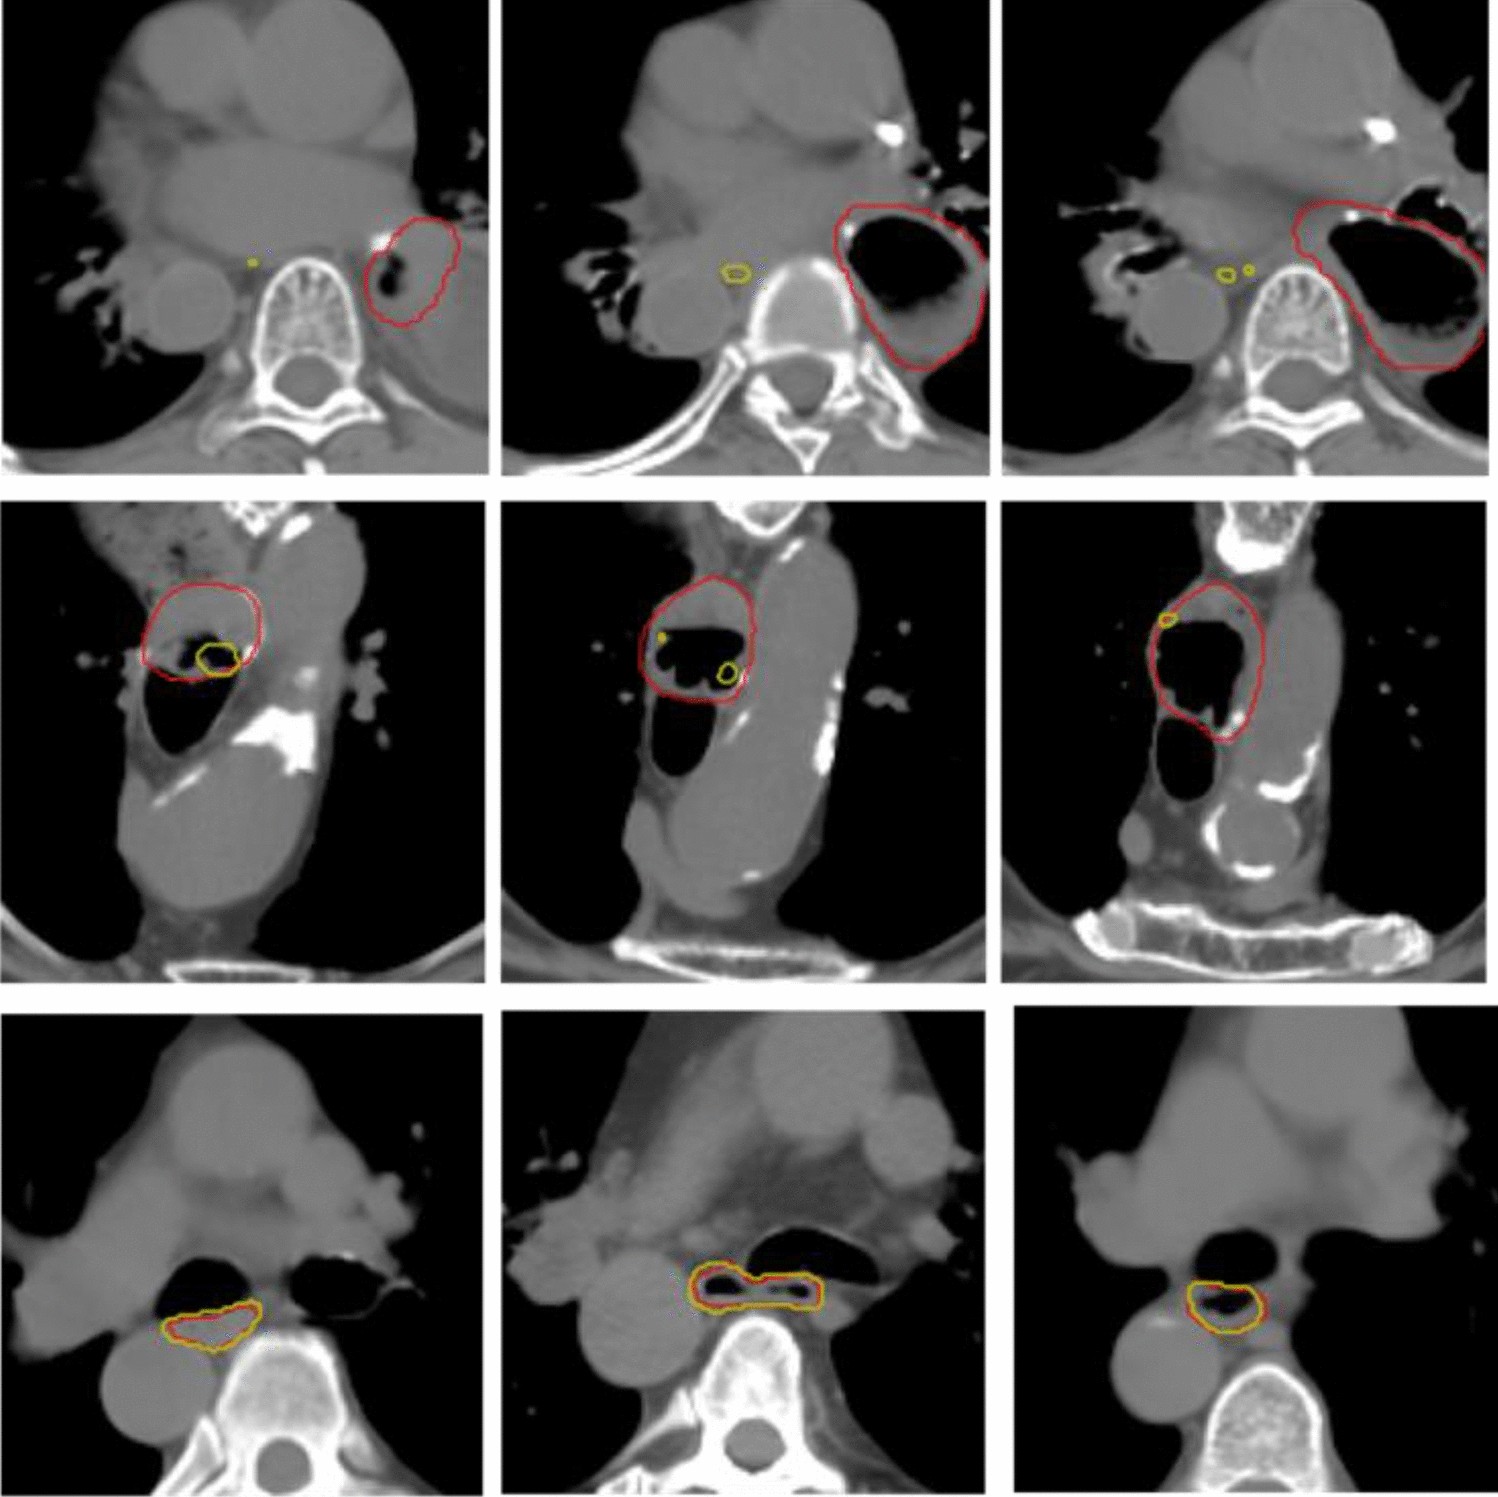

Figure 6

The top two rows are example axial slices for the demonstration of air bubble issue from two patients. The bottom row demonstrates accurate predictions from other patients. (red: ground truth; yellow: model prediction).